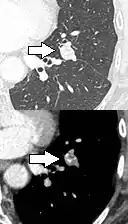

Calcifications and popcorn-like appearance, conferring a diagnosis of hamartoma.[9]

• In case of calcifications, a popcorn-like appearance indicates a hamartoma, which is benign.[3]